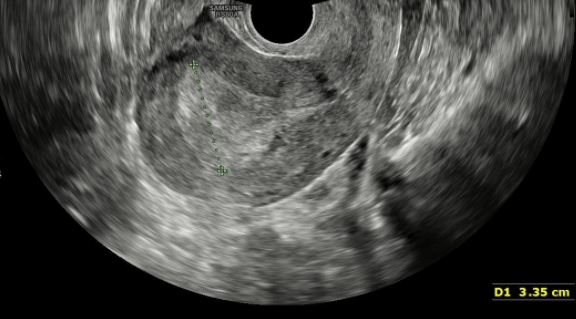

Espessamento endometrial no ultrassom transvaginal

Esta medida é realizada por meio do ultrassom, sendo que a espessura endometrial normal nas mulheres na menopausa é de até 4 mm.

Mulheres que ainda menstruam o aspecto do endométrio no ultrassom é mais importante que a medida da espessura endometrial e, por isso, a avaliação de um especialista é fundamental para se discutir a conduta, diante de sintomas associados ao espessamento endometrial.